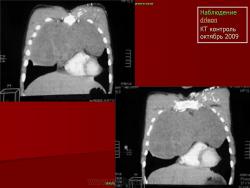

НАБЛЮДЕНИЯ КОЛЛЕГ

1.

2.